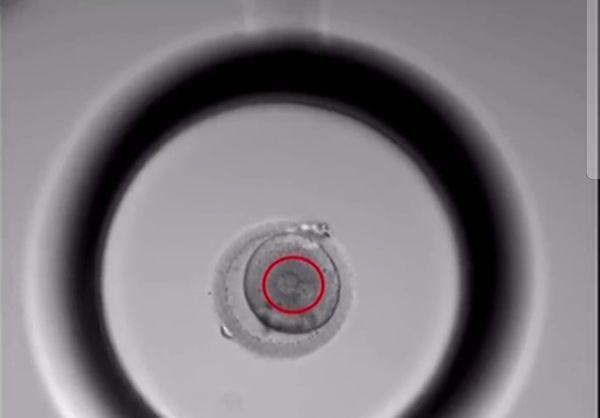

胚胎培养第1天半:精卵结合后形成了受精卵,清晰可见两个细胞核